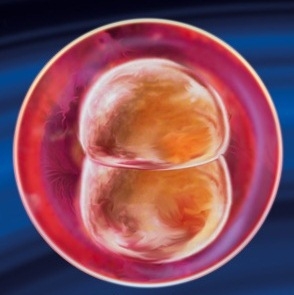

Topošās mātes ķermenī notiek brīnums. Vienīgā šūna tiek fiksēta dzemdes dobumā un sāk strauji sadalīties. Vienšūnu embrijs kļūst daudzšūnu (tā sauktais morula). Ļoti drīz tiks ieliktas topošā bērna ķermeņa vissvarīgākās sistēmas.